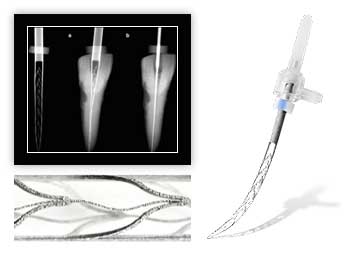

Наше оборудование

Как проходит лечение под микроскопом

При лечении зубов под микроскопом пациенту не нужно сидеть в стоматологическом кресле. Он располагается лежа удобно на кушетке. Стоматолог работает за головой или располагается справа, а на расстоянии в 20-25 сантиметров находится микроскоп. Изображение также транслируется на мониторе, чтобы ассистент мог передавать врачу препараты и инструменты, необходимые по ходу лечения.

Преимущества использования микроскопа в стоматологическом лечении

Эффективность лечения зубов под микроскопом во много раз выше, чем при использовании стандартных методов. Стоматолог может удалить только пораженные участки, не затронув здоровые ткани. Применение современного оборудования с качественной оптикой обеспечивает:

- точную диагностику — кариес можно обнаружить на ранней стадии, не останутся незамеченными дефекты пломб, трещины и другие особенности;

- щадящее удаление тканей — здоровые останутся не тронутыми;

- высокое качество терапии, что особенно важно при лечении каналов зуба;

- точность стоматологических манипуляций.